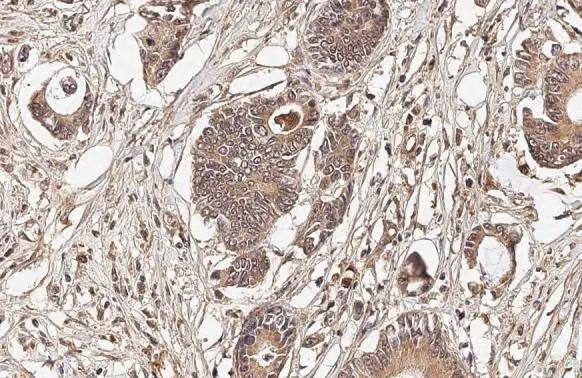

Immunohistochemistry-Paraffin: OASL Antibody (HL2399) [NBP3-25583] -

OASL antibody [HL2399] detects OASL protein at cytoplasm by immunohistochemical analysis.Sample: Paraffin-embedded human colon cancer.OASL stained by OASL antibody [HL2399] (NBP3-25583) diluted at 1:100.Antigen Retrieval: Citrate buffer, pH 6.0, 15 min